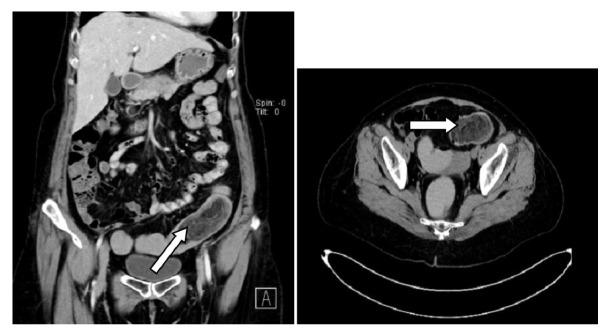

Most of the colonic submucosal mesenchymal polyps are benign tumors. They are formed by more than one type of mesenchymal tissue. The diagnosis of angiolipofibroma depends on the histological findings with the proliferation of vascular, fatty, and fibrous connective tissues. Majority of angiolipofibromas are arising in the kidney and have rare presentation as extra renal region. Here we report a case of 58-year-old female patient with angiolipofibroma of sigmoid colon (8.5 cm x 4 cm size) which was treated successfully with surgical resection. The clinical presentation, operative procedure, pathological features, and medical literature review are presented.

大多数结肠黏膜下间质息肉是良性肿瘤。它们由不止一种类型的间质组织构成。血管脂肪瘤的诊断取决于血管、脂肪和纤维结缔组织增生的组织学表现。大多数血管脂肪瘤发生于肾脏,在肾外区域表现罕见。在此,我们报告一例58岁女性患者,患有乙状结肠血管脂肪瘤(大小为8.5厘米×4厘米),经手术切除成功治疗。本文介绍了临床表现、手术过程、病理特征以及医学文献综述。